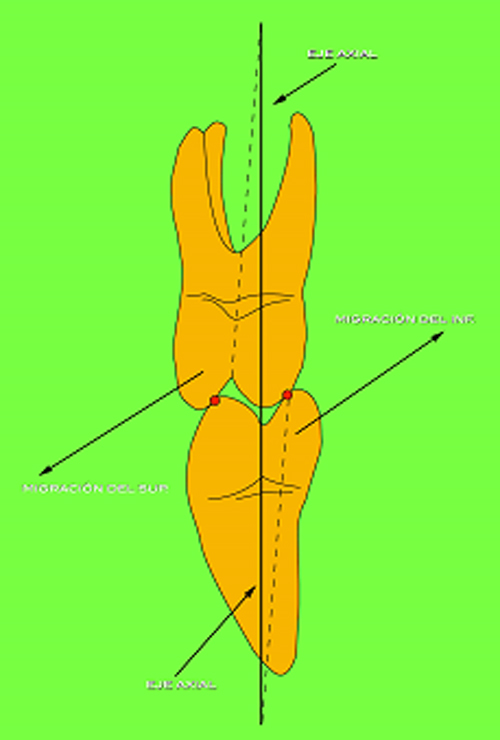

En ciertas áreas del saber humano, el lenguaje confuso o criptográfico Muchas son las técnicas elaboradas para lograr un desgaste selectivo, y numerosos autores han expuesto en su momento variadas formas de lograr una función oclusal fisiológica mediante el ajuste de la misma. Han pasado años desde entonces y, sin embargo, aún hoy, un altísimo porcentaje de profesionales “navega” por el mar de la confusión oclusal, dada la diversidad de conceptos y escuelas, sin lograr arribar a costa alguna donde poder anclar un conocimiento sólido sobre cómo tratar la oclusión Ya se esté realizando una simple obturación, endodoncia, incrustación, radectomía u ortodoncia, la lógica pocas veces, en la mayoría de los casos, vincula un tratamiento con otro, siendo el resultado final el mismo caos inicial; enmascarado por mucho tratamiento profesional. El ajuste oclusal es un medio inicial de proveer al sistema enfermo de: Dicha técnica, que puede ser terapéutica en sí misma; consta de dos etapas, a saber: 1) Ajuste Oclusal por Adición Mediante el estudio de la guía anterior, encargada de efectuar las Disclusiones durante las excursiones mandibulares, podremos observar si ésta es funcional o no. • Marcas de carácter continuo, si en ese recorrido se produce la Disclusión de los sectores posteriores y todo marcha correctamente. FIG 1-2 Si por el contrario observamos: • Marcas de carácter discontinuo, significa que dicha Disclusión se está efectuando por medio de una pieza dentaria posterior a la guía anterior. FIG 3-4-5 (FIGS. 3, 4 Y 5). En la figura 6 las flechas indican, en un caso clínico de análisis oclusal, la presencia de marcas discontinuas que indican Interferencias en Propulsiva. FIG 6-7 Y por último, si existieran: • Abrasiones de las áreas discluyentes en las áreas de diagnóstico de la guía anterior, deberemos aportar material a dicha zona para no permitir el choque lateral de las piezas posteriores (Ajuste Oclusal por Adición) En las imágenes 11 y 12 podemos observar la adición de composite en la punta de un canino derecho, previa la observación de la Faceta Parafuncional remarcada durante el análisis oclusal en el articulador. (FIGS. 8 A 12). 2) Ajuste oclusal por Sustracción o Desgaste Habiendo cumplido ya con la verificación de la funcionalidad de la Guía Anterior, comenzamos los desgastes en céntrica, a fin de lograr un único arco de cierre, guiado eficazmente por la Guía Anterior; es decir: la coincidencia entre Oclusión Habitual y Oclusión en Relación Céntrica. En este caso, intentar gastar dichos puntos, de ser posible sólo en las cúspides de corte o no fundamentales: • Crestas Triangulares Internas, Cúspides Vestíbulares Superiores • y un poco de las Crestas Triangulares Internas, Cúspides (FIGS. 13 A 16). Si la deflección es hacia el lado opuesto, se invierten los desgastes. En las migraciones hacia adelante, las únicas razones posibles están en los puntos estabilizadores (FIG. 17); es decir: -Vertientes Distales de los Rebordes Marginales, Triangulares (FIG 17) (FIG 18 A-B-C-D) Obsérvese cómo, en una boca prácticamente entera, comienzan a “desmoronarse” prismas adamantinos (FIG. 19), como consecuencia de un punto prematuro de contacto, ubicado en la posición de un estabilizador, que provoca la discrepancia horizontal postero-anterior causante de dicho efecto (FIG. 20). FIG 19-20 Dicho punto, será necesario ajustarlo antes de cualquier tratamiento en la zona ¿Cuáles serían las consecuencias si esos incisivos fueran implantados tal como es frecuente observar en múltiples congresos y cursos de implantología, donde el tema de la oclusión no es más que un cuadro polifacético y anecdótico? 14 15 16 17 Todo producto del adelantamiento mandibular Realizados ya los desgastes en céntrica, obteniendo de esta manera un único arco de cierre, es decir, oclusión en relación céntrica, debemos realizar el ajuste de las excéntricas, apoyando la acción de la guía anterior, para lo FIG 22 a. De un lado a otro de un mismo maxilar, la imagen es especular, o sea invertida. b. En hemimaxilares cruzados, la imagen es idéntica. Allí donde existan colisiones entre cúspides, se deberá crear un surco para que dicha cúspide antagonista migre a su través, tanto en el lado de no trabajo, como en el de trabajo y en el de propulsión. FIG 23 Es importante conservar esta parte del surco, ya que si no existieran, los contactos entre cúspides serían en superficie y no puntiformes (fig. 24). FIG 24 1. Obtener un único arco de cierre con coincidencia entre oclusión habitual y relación céntrica. 2. El cierre mandibular debe ser recibido sólo por la tabla premolar-molar. 3. Durante las excursiones funcionales es la guía anterior la que debe sufrir las fuerzas laterales. 4. De cumplirse estas dos premisas debemos obtener libertad de desplazamiento (no confundir con libertad en céntrica) a las piezas posteriores mediante la creación de surcos disclusivos. Examinadas ya las posibles migraciones mandibulares y los desgastes o aposiciones necesarios para poder ocluir en céntrica, es fundamental recordar que, previamente a todo tipo de ajuste, se ha hecho necesario ubicar a la mandíbula en relación céntrica. Para ello debemos utilizar el propio funcionalismo muscular 22 FIG 25 Y esto no significa otra cosa que: piezas dentarias estables en todos los planos del espacio, ATM centrada en la cavidad glenoidea, periodontos sin tensión, músculos en la dimensión de elongación adecuada para un fisiologismo Paz absoluta en la intimidad del Sistema Estomatognático. Y así, como corolario final, es posible establecer una regla de oro similar en importancia a la conocida formula: Forma = Función Ésta es: FIG 26 FUNDAMENTOS NEUROFISIOLÓGICOS DEL REGISTRO DE OCLUSIÓN EN RELACIÓN CÉNTRICA ( ORC) MEDIANTE EL USO DE LAMINILLAS DE LONG CUADRO

Es decir:

(Punto A) y Crestas Triangulares Internas, Cúspides Linguales Inferiores (punto C), del lado derecho.

Estampadoras (punto B), del lado izquierdo .FIG 13-14-15-16

-Vertientes Mesiales de los Rebordes Marginales, Triangulares Externas y Triangulares Internas de los Superiores

y

Internas y Triangulares Externas de los Inferiores.

Esta migración generalmente se acompaña de anomalías en el sector anterior (FIG. 18).